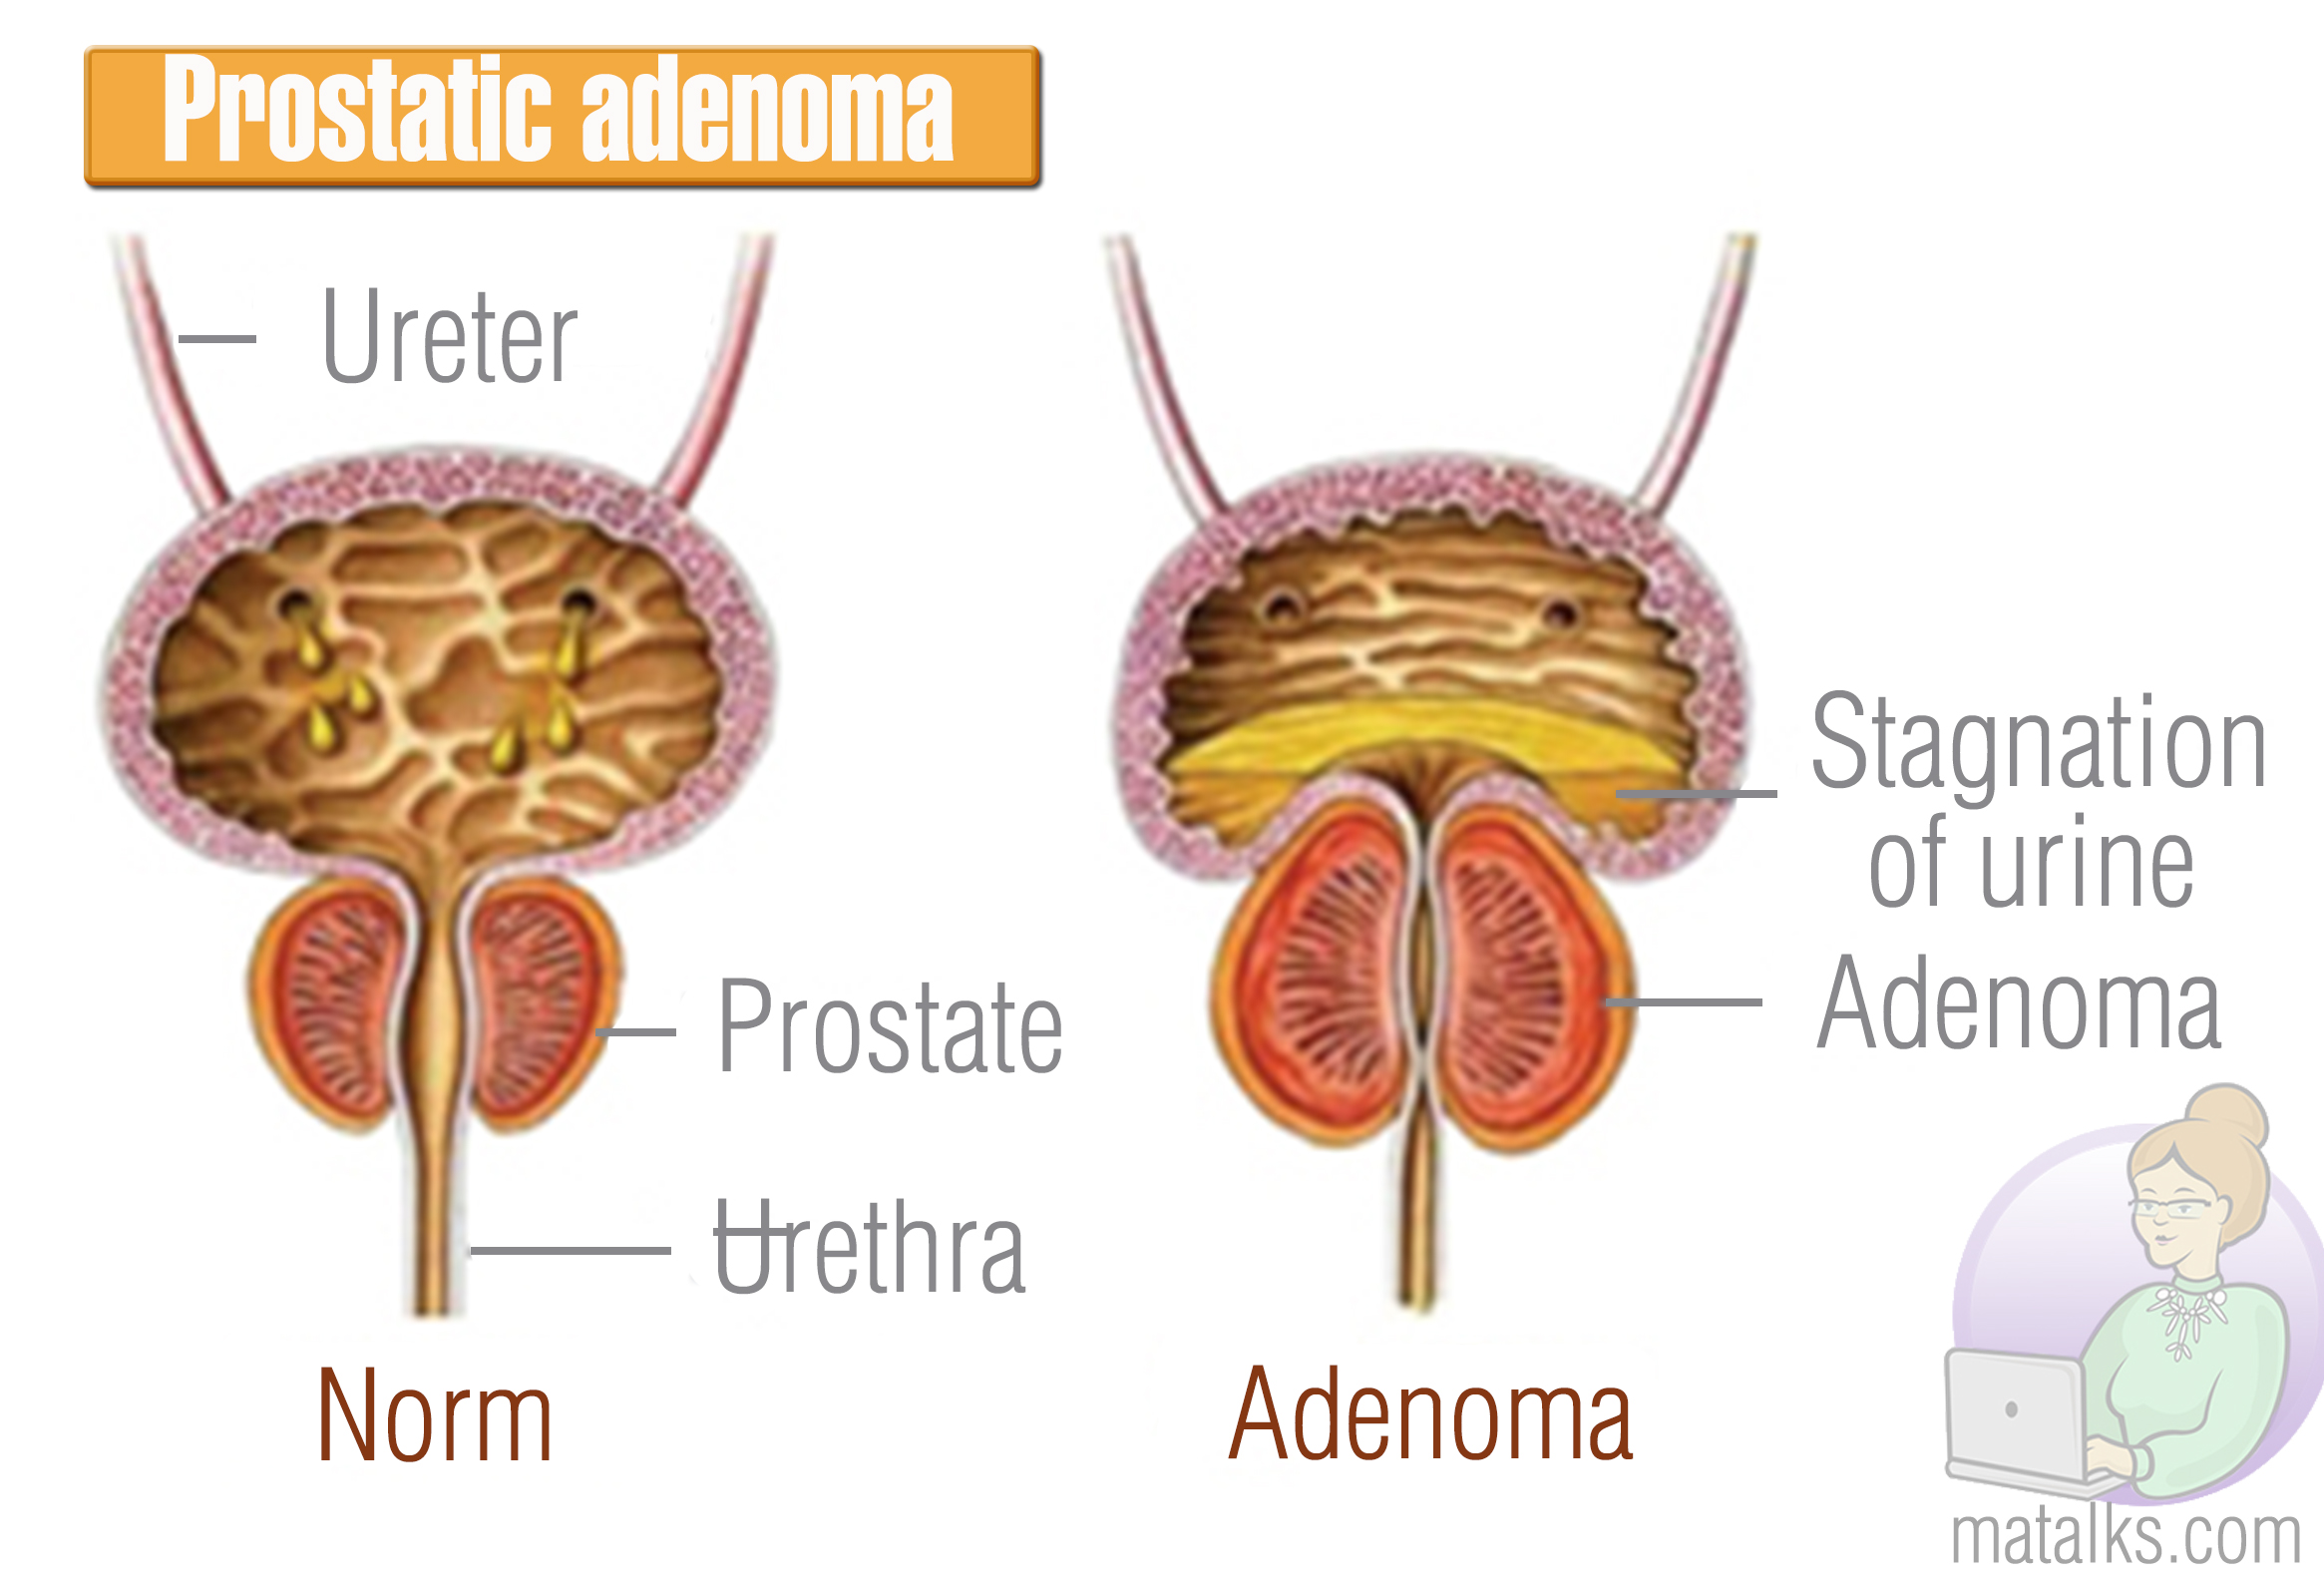

Простата, обычно ассоциируемая с мужским здоровьем после полового созревания, также присутствует у детей, хотя и в значительно меньших размерах. Этот орган, расположенный под мочевым пузырем и окружающий уретру, играет роль в выработке жидкости, которая составляет часть семенной жидкости. Несмотря на то, что проблемы с простатой у детей встречаются редко, понимание её развития и потенциальных патологий важно для ранней диагностики и лечения.